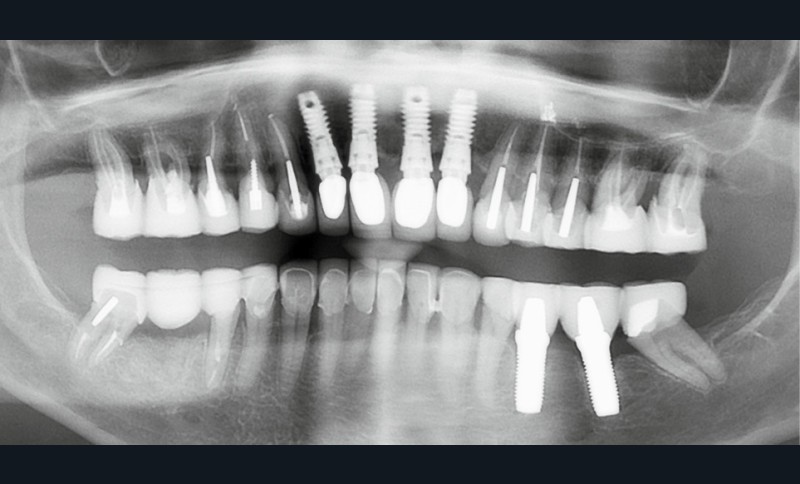

Une patiente ayant perdu ses incisives maxillaires à la suite d’un traumatisme quelques années auparavant, consulte en 2015 pour un inconfort occlusal persistant. Elle a été traitée par diverses gouttières occlusales, sans résultat notable. En 2017, une reconstruction globale est réalisée, toujours sans résolution de la plainte d’inconfort occlusal. Après avoir consulté de très nombreux praticiens et bénéficié de multiples traitements, en 2024 la patiente a perdu l’ensemble de ses dents ! En octobre 2025, après plusieurs prothèses globales sur implants, la plainte est toujours la même dans un contexte psycho-émotionnel de plus en plus difficile (fig. 1).